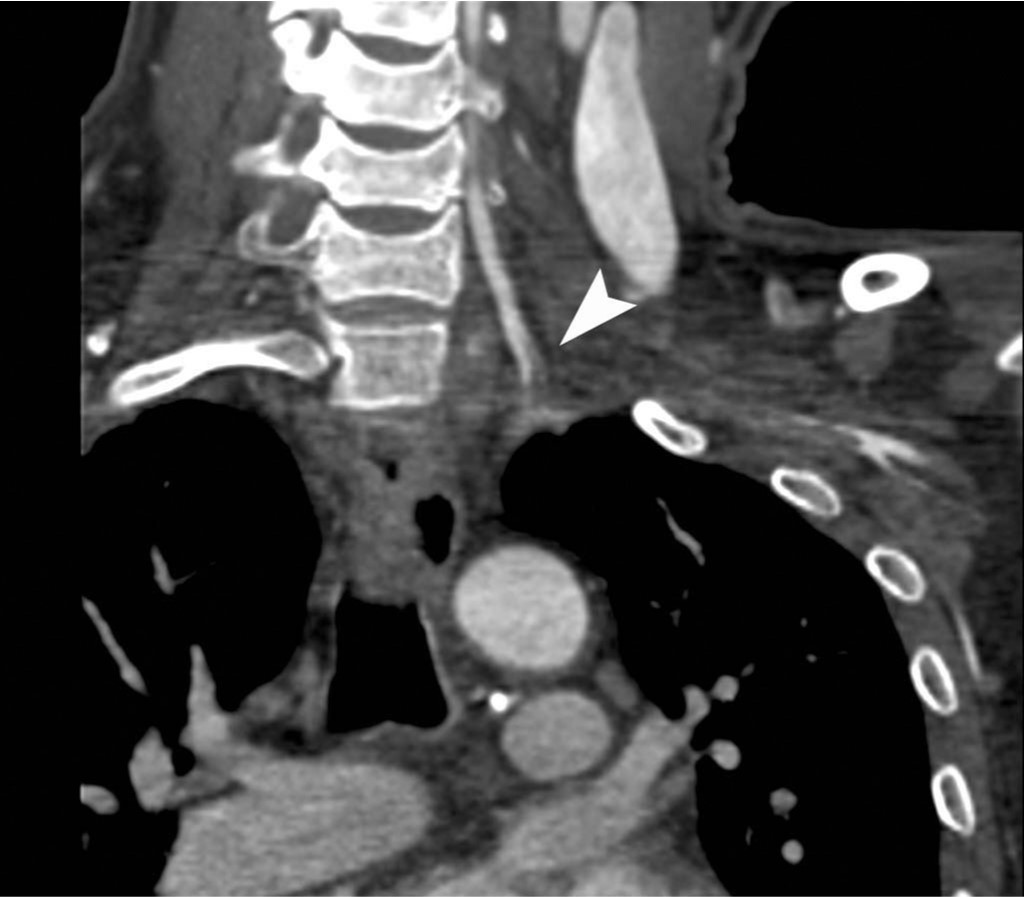

상지 CT 혈관조영술 관상면 영상에서 좌측 쇄골하동맥의 근위부에서 약 7cm에 걸쳐 혈전색전증에 의한 혈관의 부분폐쇄가 확인되고(Fig. 1A, B, C), 혈전색전증은 좌측 추골동맥 근위부로도 연장되어 있음(Fig. 1D).

Fig. 1. A-D

Fig. 1A-D Coronal CT images show a partial thrombotic occlusion at proximal subclavian artery (SCA, arrow in Fig. 1A-C), and proximal vertebral artery (VA, arrow head in Fig. 1D).